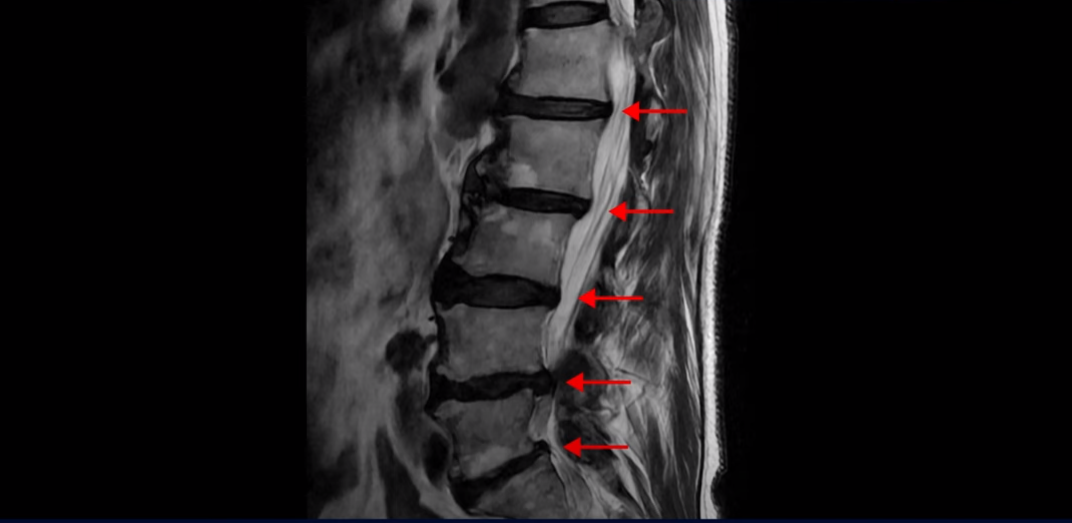

협착증은 노화 때문에 생기는 질환입니다. 나이가 들수록 노화와 퇴행 때문에 신경 구멍이 조금씩 좁아집니다. 이분도 신경 구멍이 좁아져 있습니다. 보시다시피 척추 여러 마디가 퇴행되어 있고

특히 왼쪽 신경가지가 빠져나가는 추간공들이 많이 좁아져 있습니다.